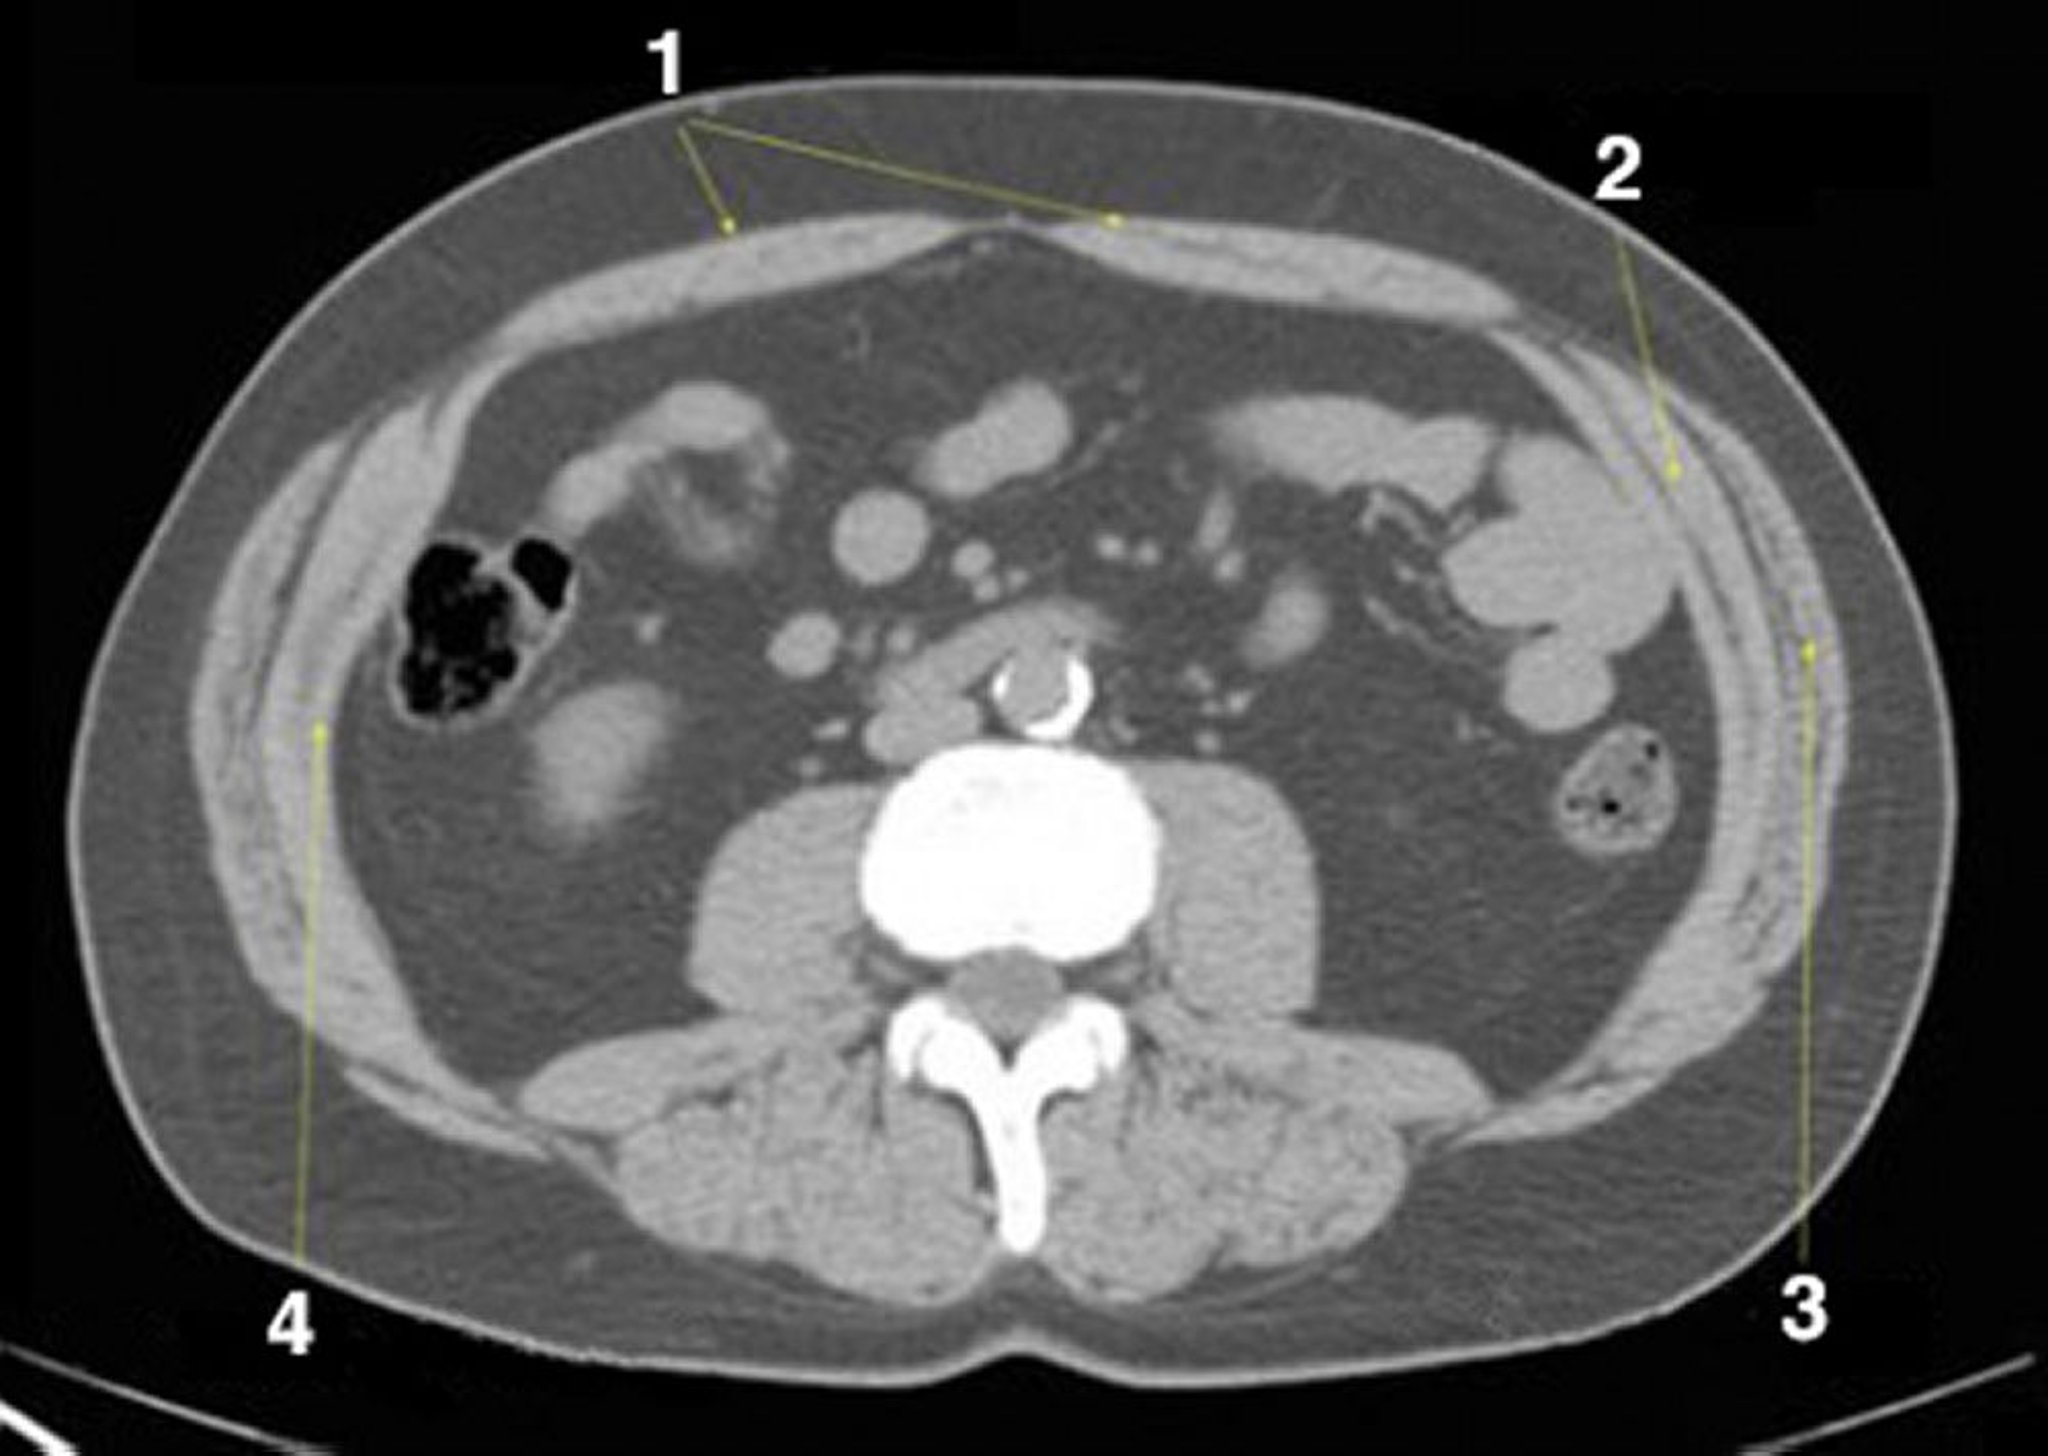

TDM sans contraste de l'abdomen et du bassin montrant une anatomie normale (diapositive 19)

1 = rectus abdominus; 2 = oblique interne; 3 = oblique externe; 4 = abdominus transverse.